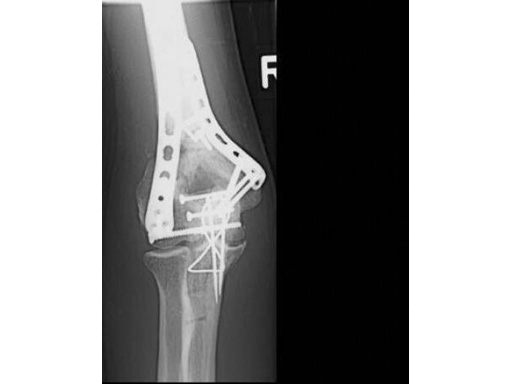

23-year-old man, 13-C3 fracture treated with DHP.